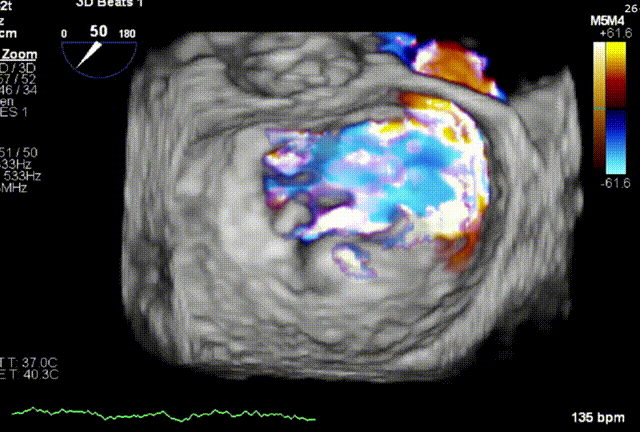

术前1区X-Plane反流情况

术前3D VIEW